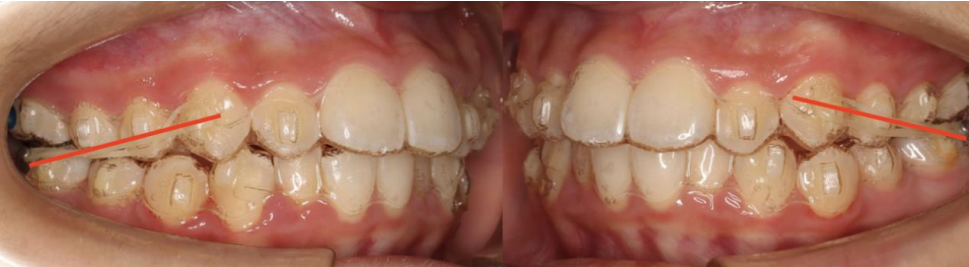

口内检查:口腔卫生良好,牙龈健康,上前牙牙列拥挤 上前牙唇倾,下前牙列拥挤;

磨牙关系:双侧磨牙远中关系;

覆合覆盖:前牙 II°覆盖;

牙列:恒牙列,上前牙唇倾,上牙弓方圆形,l 度拥挤。下牙方圆形,l 度拥挤,上下牙弓匹配,17、27、37、47 未萌出。